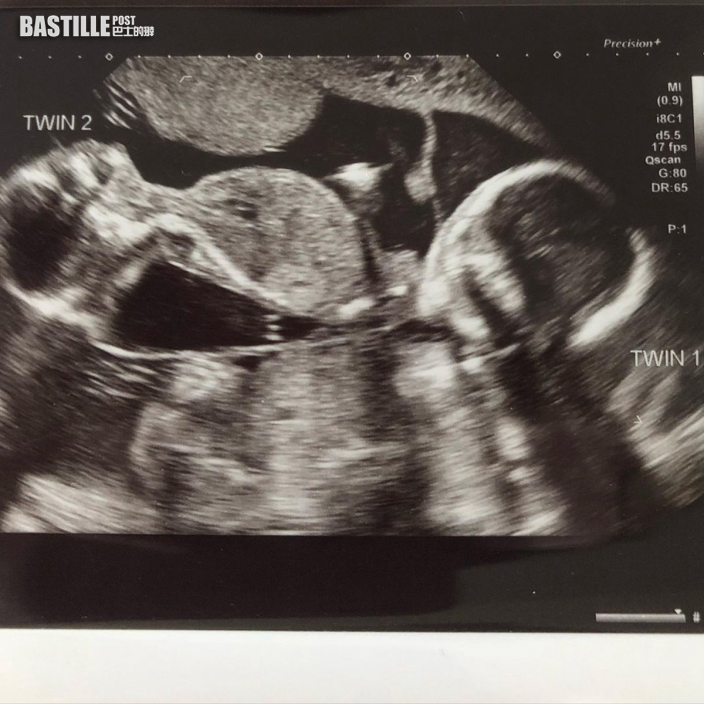

英國39歲女子Rebecca Roberts與丈夫育有一女,數年前開始再嘗試懷孕不果,至接受生育藥物治療後,終在去年迎來懷孕喜訊。她第一次進行超聲波檢查,獲醫生告知懷上單胎,但至懷孕12周時再進行檢查,竟意外發現再懷上另一胎,是非常罕見的「異期復孕」。她去年9月順利誕下一對雙胞胎,形容子女就是奇蹟的證明。

起初她第1次進行超聲波檢查時,醫生告知她懷上單胎,至懷孕12周時進行第3次檢查,卻發現子宮內出現第2個胎兒,而兩胎的懷孕時間僅相差3星期。今年39歲的Roberts直言:「得知肚內有兩個胎兒,而非一個,實在讓我太震驚。」

巴斯皇家聯合醫院(Royal United Hospital)婦產科醫生David Walker指,由於第二名胎兒的體形小很多,經多次掃瞄及檢查後始終發現她的發育較第一名如胎兒小3周,推斷出這情況為醫學界中異常罕見的「異期復孕(superfetation)」:「Roberts在第一次受孕後約3周又再排出卵子,而這顆卵子同樣受精,並植入子宮。」